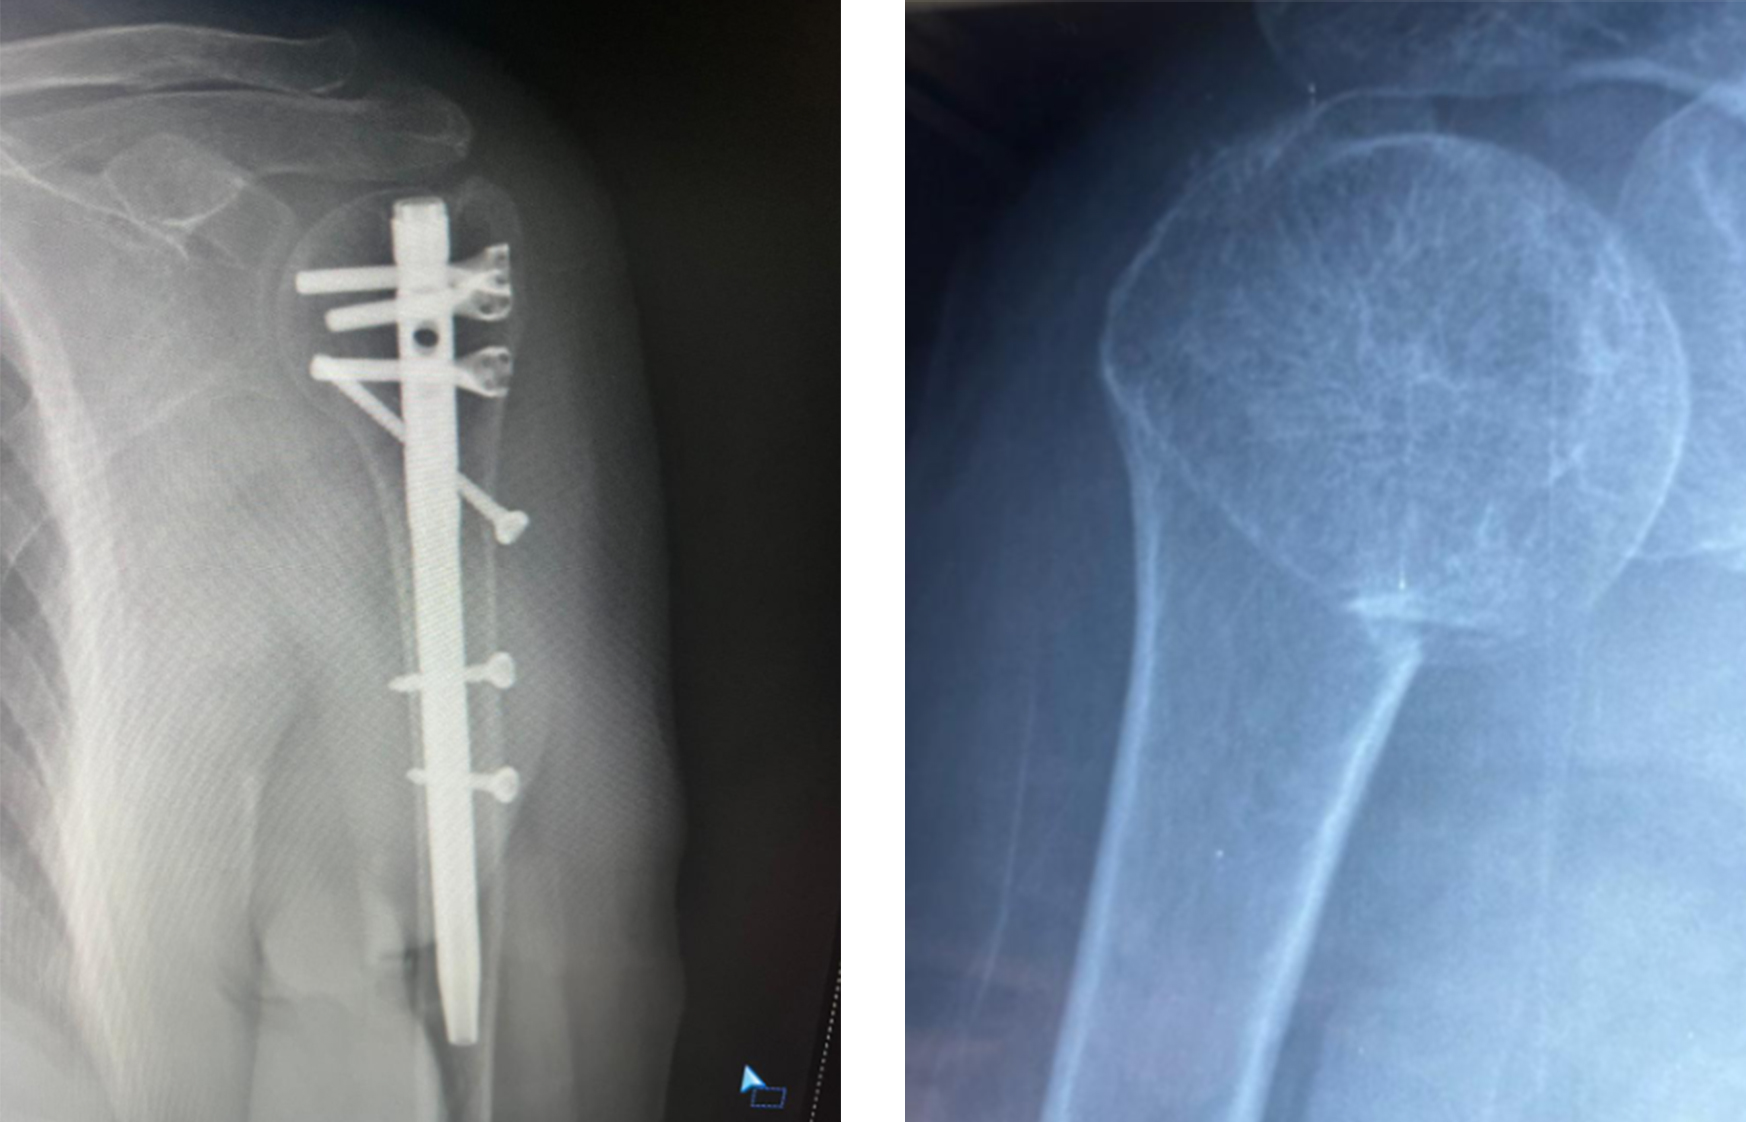

Fijación de clavos intramedulares

La fijación con clavo intramedular es una técnica mínimamente invasiva que proporciona soporte interno a través del canal medular.

cirugía ortopédica de fijación de clavo intramedular humeral.jpg

Cuando se prefiere el clavo intramedular

• Fracturas de cuello quirúrgicas

• Se requiere una alteración mínima de los tejidos blandos

• Ciertas fracturas involucradas en la diáfisis